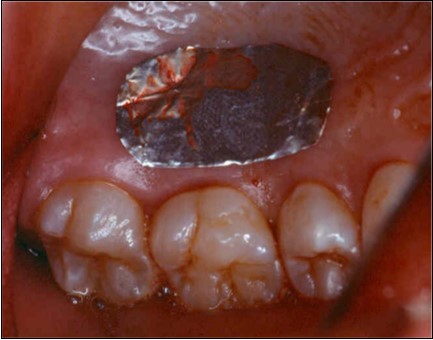

The patient under hard emotional stress that associated with bacterial plaque promoted ANUG with necrosis of alveolar bone and marginal gingival soft tissue in 31 and 41 (Figure 1). The patient was free of systemic disease and was not currently receiving any medication. Initial therapy was carried out using Er-YAG laser, to promote scaling and root planning and oral hygiene instruction. After initial therapy (Figure 2) the surgical method employed consists of the following steps as described by Langer and Langer5.

Figure 2.After initial therapy